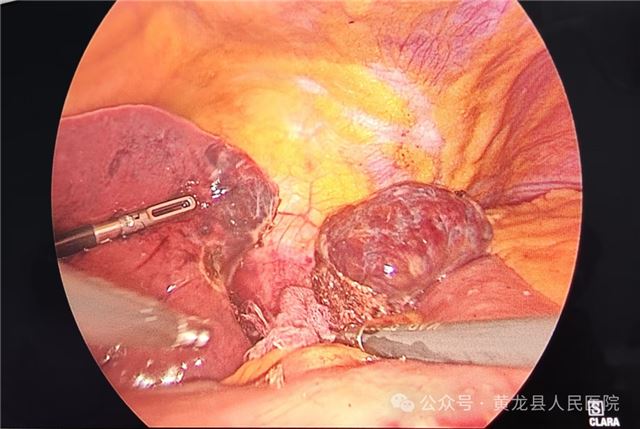

2,术中

术中探查

术后切除部分肝组织约4.5×4cm